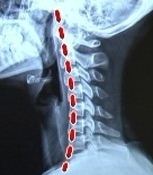

최근 한 방송에서 H컵녀가 가슴아픈 사연을 공개한적이 있는데요

H컵녀는 “사람들의 시선 때문에 몸을 구부정하게 다녔더니 뼈가 목부터 허리까지 휘어져 있다”며

작은 체구에 비해 가슴이 무거워 중심이 자연스레 앞으로 쏠리게되면서

목뼈와 허리쪽 근육등의 상태가 많이 안좋았다고해요~

위의 사진에서 보시다시피 H컵녀와 정상인의 촬영한 화면은

눈에 띄게 다르다는 것을 느끼실수 있습니다